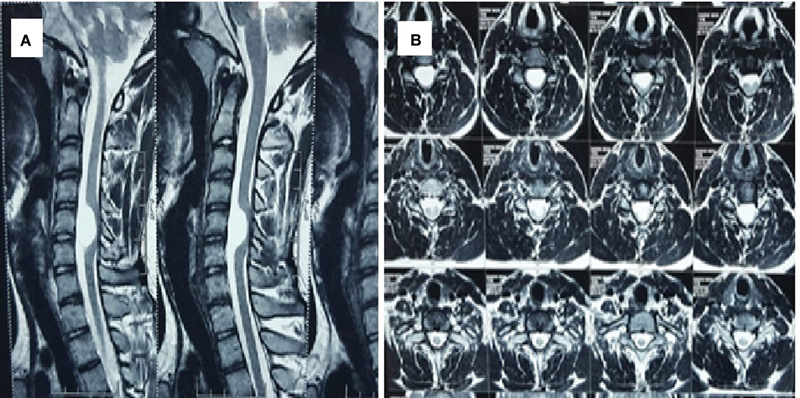

An arachnoid cyst is mostly congenital CSF-filled space occurring in the brain and spine. In the spine, they are usually found in the posterior aspect. Anterior cervical arachnoid cyst is very uncommon. A 14-year-old adolescent boy presented with rapidly progressive quadriparesis starting with the left lower limb, which is associated with radiating pain and numbness in both upper extremities. There was no sensory deficit, and the bladder and the bowel were normal. The radiological evaluation with contrast-enhanced MRI was suggestive of an anterior cervical intradural arachnoid cyst, for which the patient underwent surgery with wide fenestration and partial removal of the cyst wall, and the cyst wall was sent for histopathological examination. The patient improved postoperatively without any residual deficit. Anterior cervical arachnid cyst is a very rare lesion and should be considered in children and young adults who presented with neck pain or radiculopathy, especially if they are followed by motor weakness.